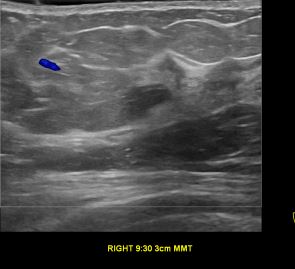

상기환자는 우측 유두분비물 있어 정밀검사위해 내원하신 60대 중반 여성분으로 우측양성종양 절제술 시행해 유방암으로 진단 되었습니다